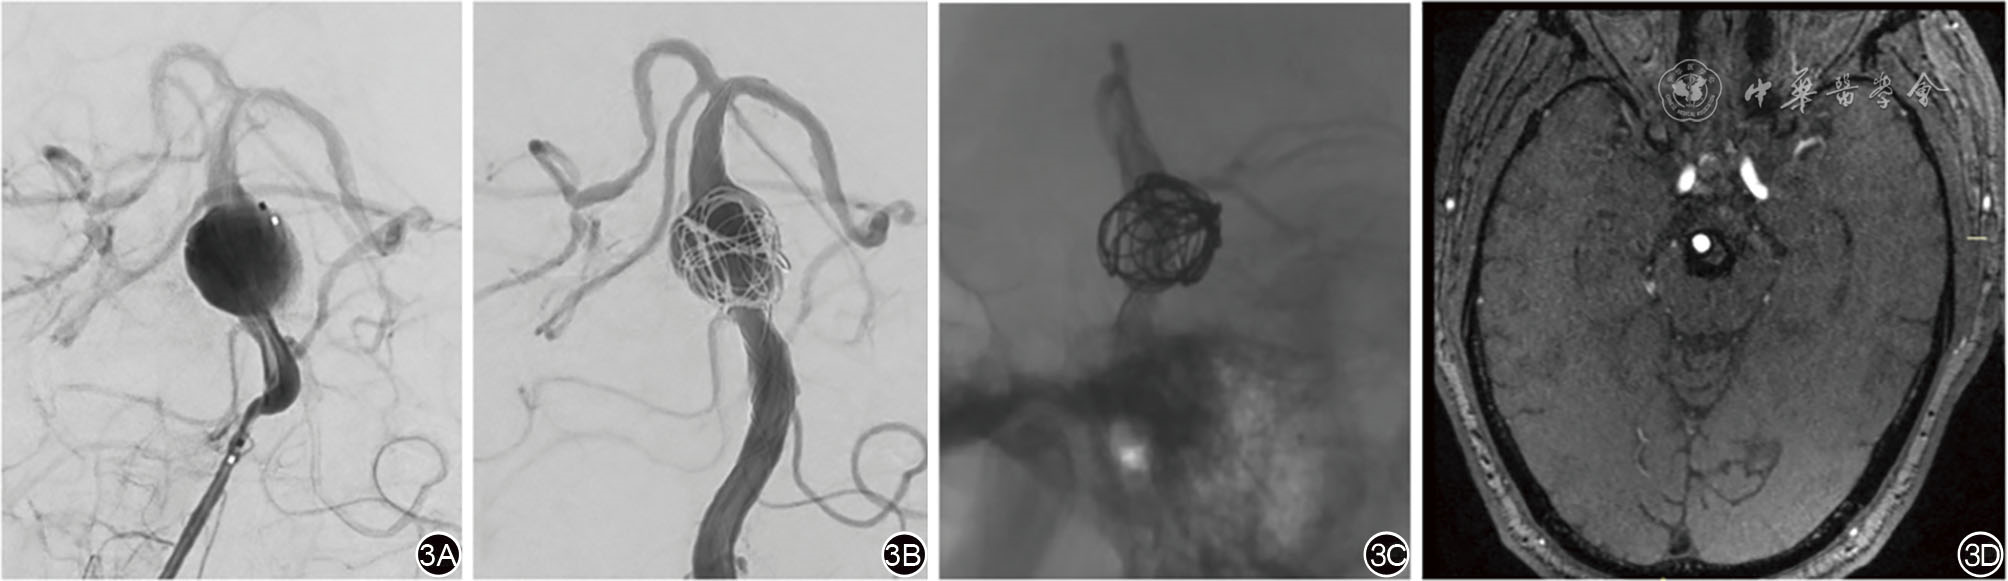

图3 重叠Leo支架治疗基底动脉中段节段扩张型基底动脉夹层动脉瘤 3A:基底动脉主干中段一枚节段扩张型夹层动脉瘤;3B:使用双Leo-plus支架重叠技术,术后造影示仍有血流进入瘤腔;3C:复查时瘤腔内无血流进入。3D:术后18个月高分辨血管壁磁共振示瘤腔内未见血液充盈。